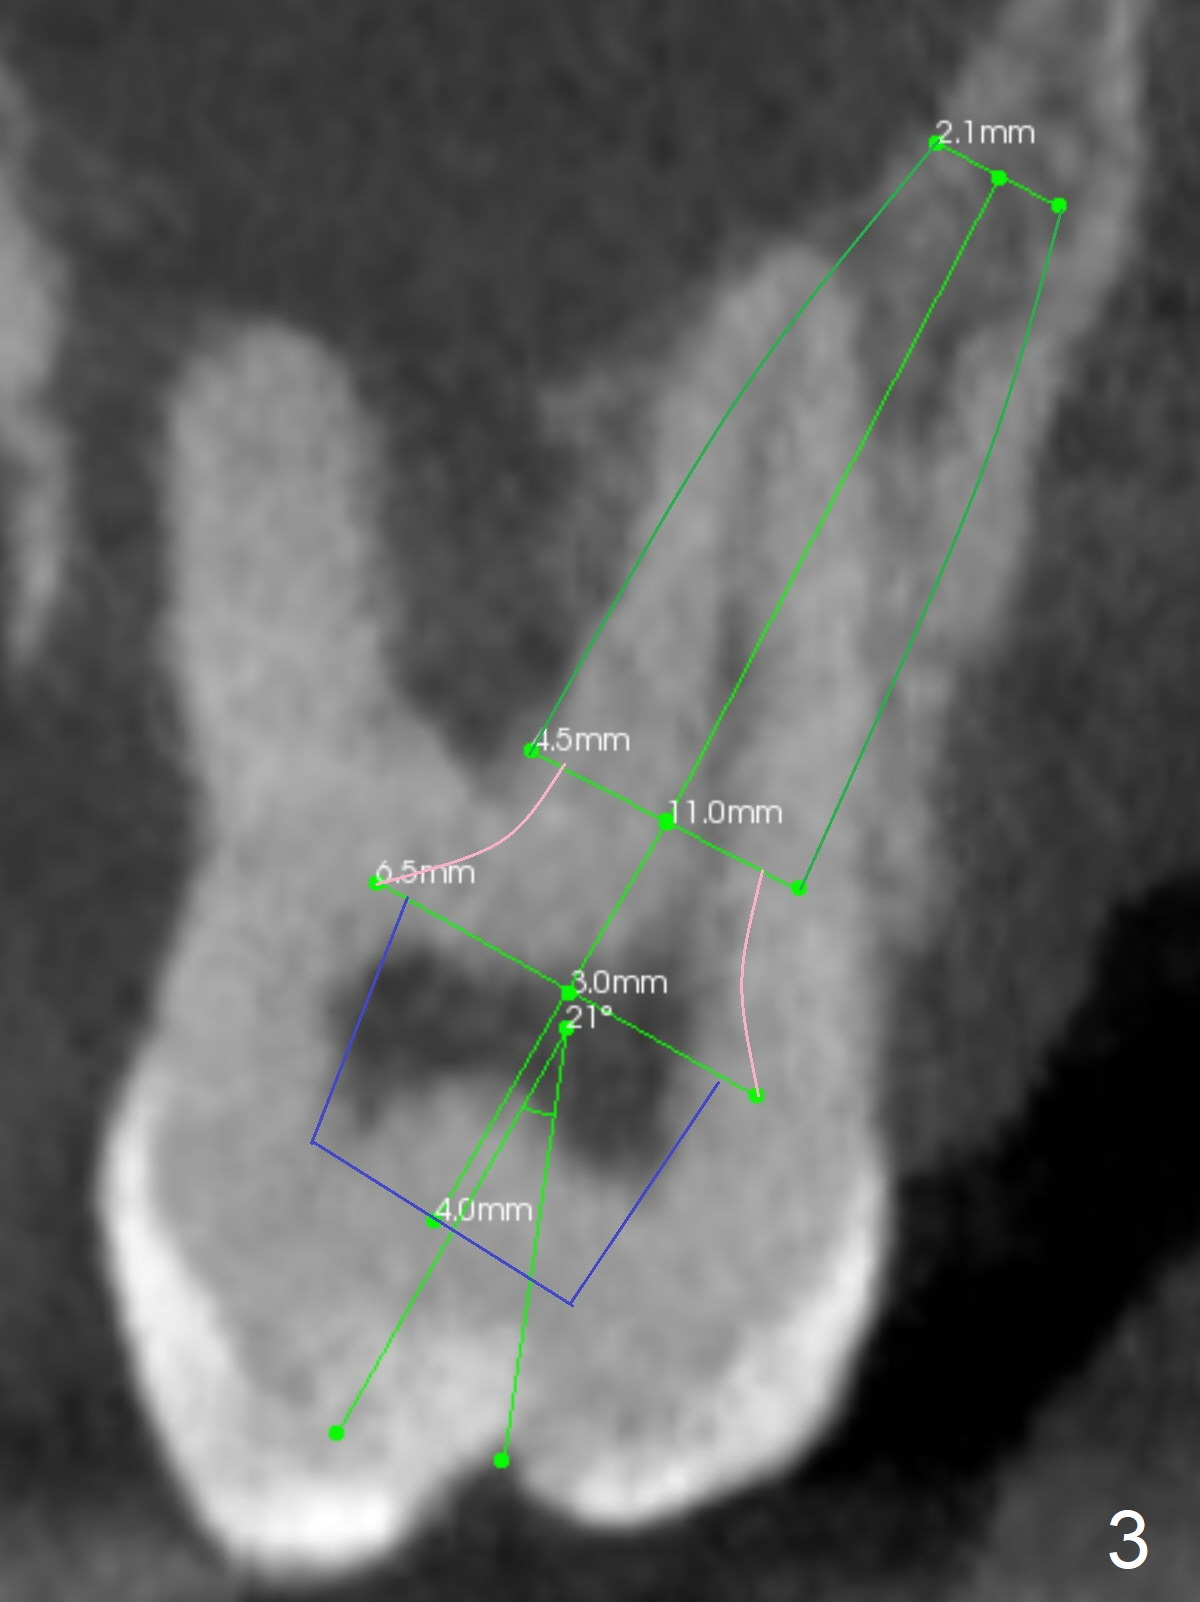

A 40-year-old man develops an abscess around the buccal roots of the tooth #15 several years after extraction of the symptomatic tooth #16. The pattern of infection is similar to that between #17 and 18. There is severe bone loss (Fig.1 *) around the fused buccal roots (Fig.2). It appears that an immediate implant (green) placed in the septum (Fig.4) has better position and angulation for restoration than the one placed in the palatal socket (Fig.3). Pink: cuff of abutment (blue); yellow: Osteogen Plug; red: bone graft.